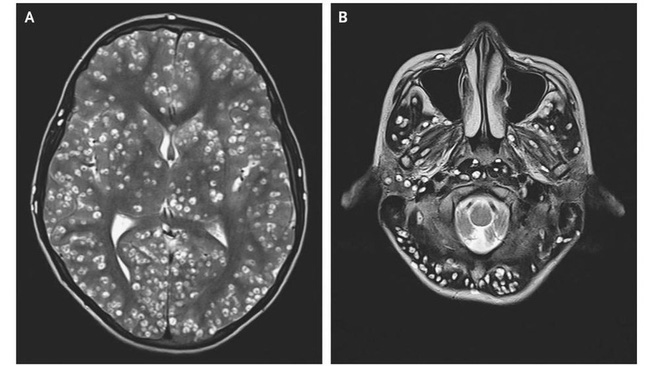

Những vệt màu trắng chính là sán dây đang dần xâm chiếm não và gây bệnh (Ảnh minh họa).

Trường hợp của người phụ nữ này cũng tương tự như tình trạng của anh Zhu Zhong-fa trước đó không lâu. Theo foxnews, anh Zhu đã đến bệnh viện Đại học Chiết Giang (Trung Quốc) do liên tục bị đau đầu và co giật mãi không khỏi. Tới lúc bác sĩ tiến hành chụp Xquang mới phát hiện có hàng trăm con sán dây đang bò lúc nhúc trong não và ngực của anh.